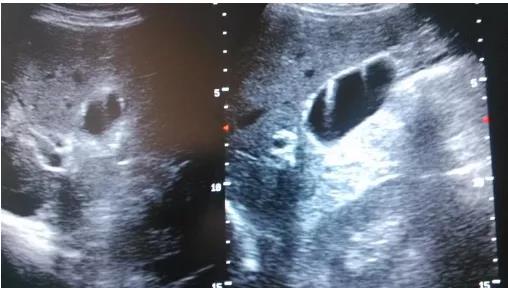

①看真假:真正可能變癌的是真息肉,假息肉不用管;

②看大小:長到1厘米了就需要考慮手術(shù),風(fēng)險(xiǎn)大了;